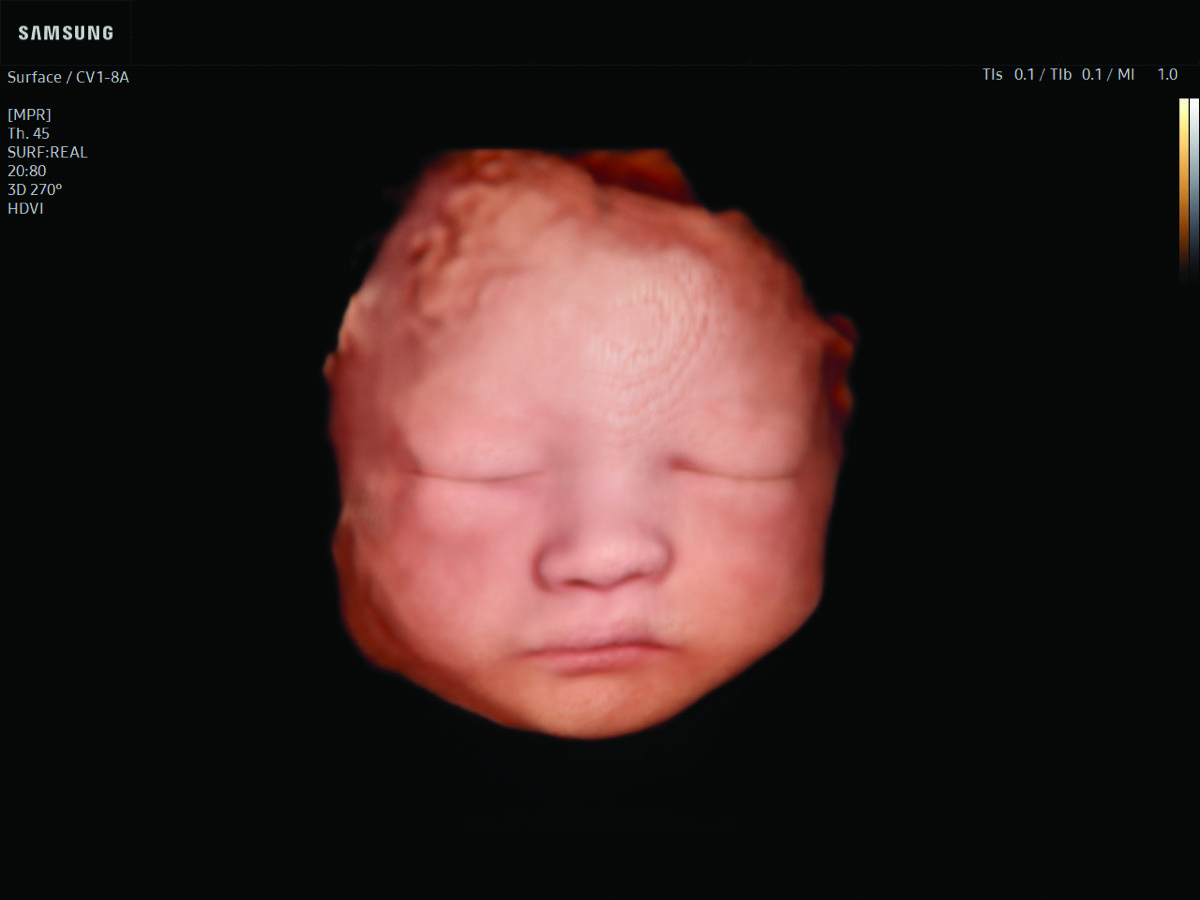

Comprehensive, advanced and expert MFM care for high-risk pregnancies